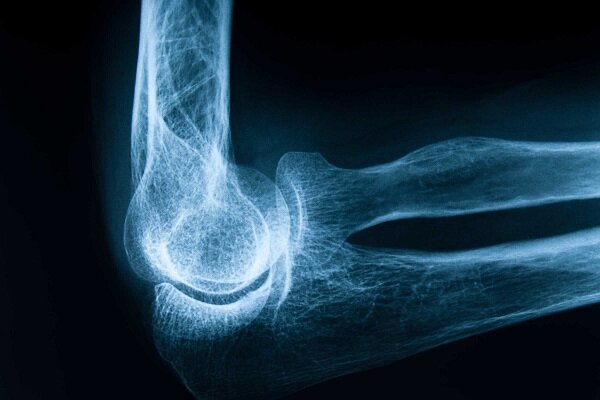

به گزارش خبرگزاری ایمنا، پوکی استخوان یا پوکی استخوان یک بیماری مزمن و پیشرونده است که با کاهش تراکم و کیفیت بافت استخوانی، ساختار استخوان را شکننده و آسیب پذیر می کند. این بیماری اغلب بدون علائم بالینی خاص پیشرفت می کند و تا زمانی که شکستگی رخ ندهد ممکن است فرد از وجود آن بی خبر باشد. شکستگی های ناشی از پوکی استخوان، به ویژه در نواحی لگن، ستون فقرات و مچ دست، می تواند منجر به درد مزمن، ناتوانی حرکتی، بستری شدن طولانی مدت در بیمارستان و حتی افزایش خطر مرگ در سالمندان شود و بنابراین، پوکی استخوان نه تنها یک مشکل استخوانی است، بلکه یک چالش جدی برای سلامت عمومی است.

تشخیص زودهنگام پوکی استخوان از طریق اندازه گیری تراکم استخوان با روش DXA.جذب رادیوگرافی دوبل) امکان پذیر است، این آزمایش تراکم استخوان را در نواحی حساس مانند لگن و ستون فقرات اندازه گیری می کند و خطر شکستگی را پیش بینی می کند و طبق توصیه های بین المللی، زنان بالای 50 سال، مردان بالای 70 سال و افراد دارای عوامل خطر باید به طور منظم غربالگری شوند، همچنین بررسی سابقه خانوادگی، مصرف برخی داروها و بیماری های زمینه ای در ارزیابی خطر فردی مهم است.